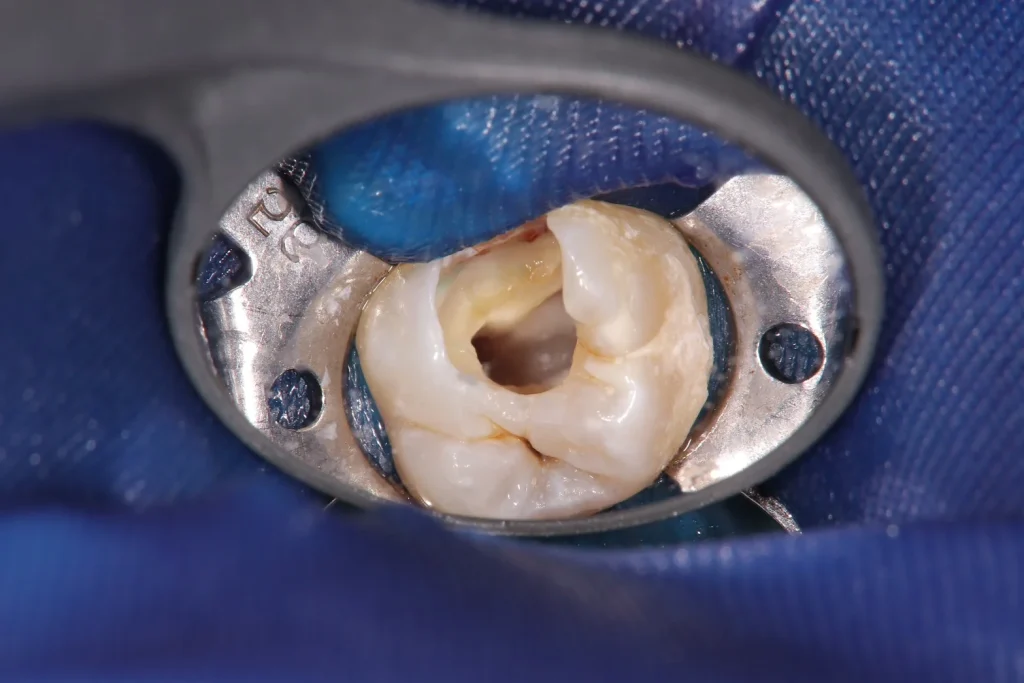

ラバーダム防湿とは、治療する歯以外に薄いゴム製のシートをかぶせて 唾液や菌による治療箇所の感染を防止する器具です。 ラバーダムを使う事で、様々な菌が治療箇所に侵入する事を防ぎより精度の高い治療を行う事が可能になります。

海外では、根管治療においてラバーダムを使用することは当たり前になっておりますが、 日本では実施している歯科医院はかなり少ないです。 当院では、根管治療の際にラバーダムを可能な限り使用し治療を行っておりますので、ご安心ください。